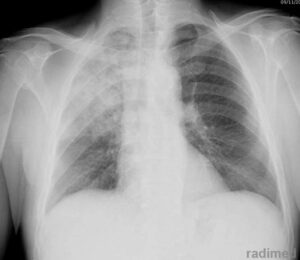

Quando si ha pneumotorace quello che accade è un abolizione delle vibrazioni vocali e delle murmore vescicolari, timpanismo alla percussione e iperclarità radiologica.

Da un punto di vista radiologico si apprezza iperchiarità dell’aria, il moncone di polmone e la deviazione del mediastino.